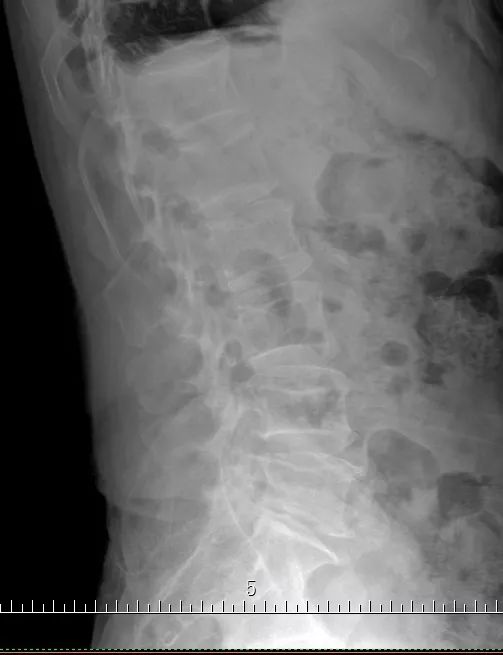

术前的磁共振及X光片

今天要给大家介绍的是82岁的盛老伯。孝顺镇某村人。时不时有腰痛不适的感觉已多年。近3多个月来,腰痛逐渐加重,并出现左下肢的麻木和疼痛,走路不方便,稍走远一点,左下肢就疼痛难忍,需要歇一会才能继续行走。为了减轻疼痛,必须弯腰走路。曾经用过许多药物及针灸治疗,但是不见好转。十多天前到仁康医院就诊,拍片及磁共振检查发现腰椎第四、第五节之间明显骨质增生,同时有椎间盘突出,椎管狭窄。由于神经压迫明显,只能通过手术,取除突出的椎间盘,扩大狭窄的椎管,才能解除症状。